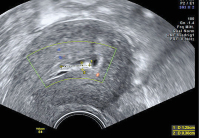

Ultraschall-Serometra

Abbildung 3: Selber Fall wie Abbildung 2 mit 3D-Ultraschall: Zwischen einem dünnen, echodensen Randsaum aus Endometrium hat sich eine Ansammlung von Flüssigkeit mit länglichen, echodensen Strukturen gebildet. Der Stimulationszyklus wurde abgebrochen.